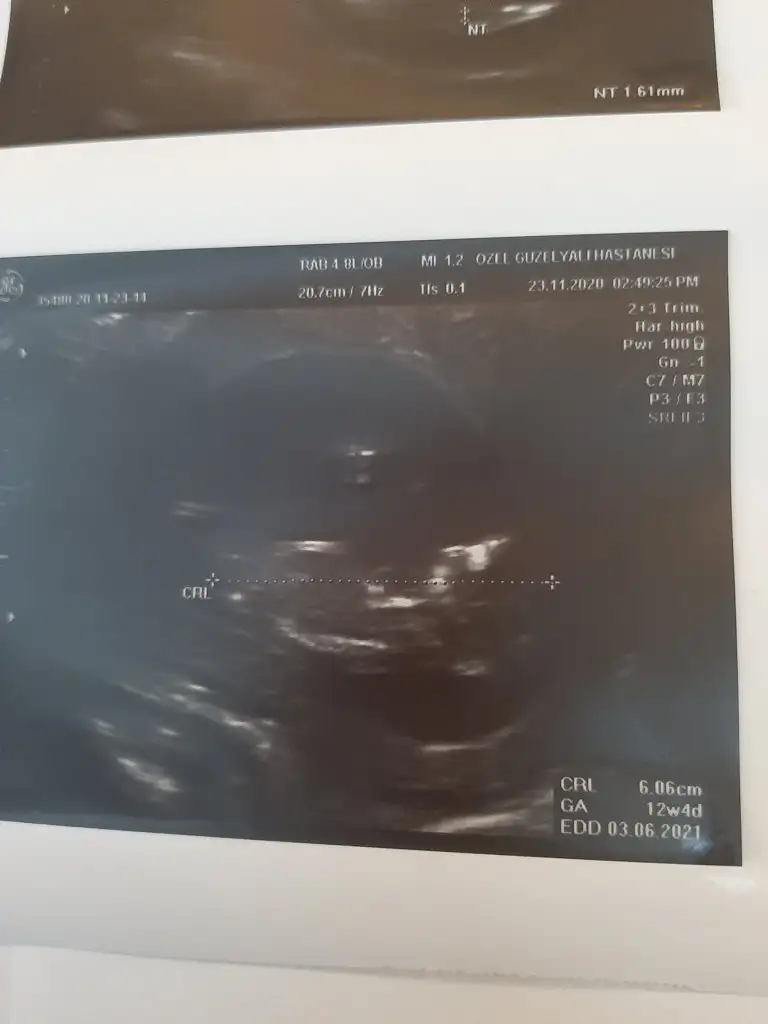

Lütfen bana da yorum yapar mısını?Ben ama size sürekli 11 12 13 haftalar olmalı diyorum

Evet erkek dik görünüyorLütfen bana da yorum yapar mısını?doktor erkek olabilir dedi 12+1 deki ve 12+4 deki ultrason resimleri

Kese yapısı değişiyormu acaba surekli fasulye seklini yuvarlak gordum dger gün şaşrdmErkek gibi ama en iyi 11 12 13 haftalar olmalı